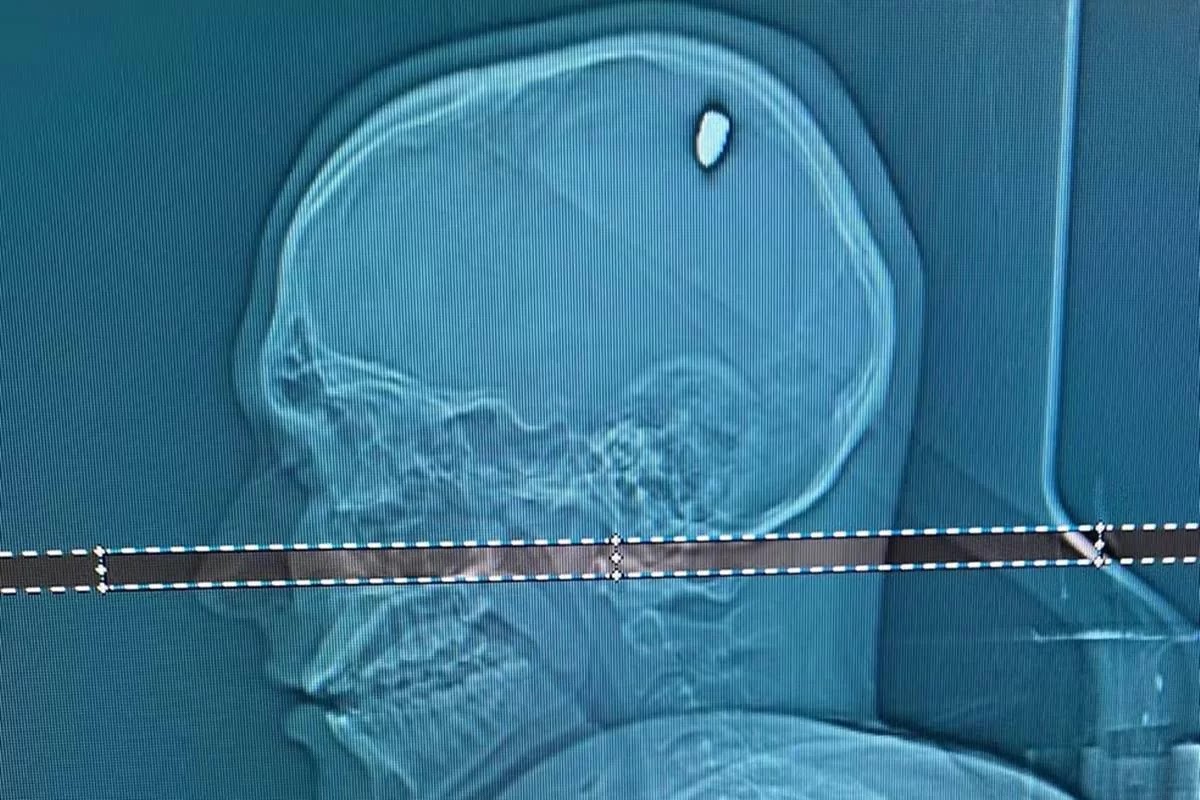

Um exame de tomografia mostrou que Mateus estava com uma bala alojada na cabeça. “Parte dela penetrou no cérebro. Isso causou compressão da região, e os movimentos involuntários do braço”, explica o neurocirurgião Flávio Falcometa.

A cirurgia para retirar o projeto ocorreu em Minas. Durou cerca de duas horas, e o paciente ficou internado na unidade de terapia intensiva (UTI).

“Por poucos milímetros, ela poderia causar um dano bem mais grave, como ficar com o braço paralisado ou metade do lado do corpo paralisado. Foi arriscado, bem arriscado para o paciente. A gente acredita que em 20, 30 dias, ele vai seguir com a vida normal dele”, completou o neurocirurgião.